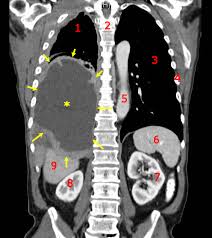

Asbestos And The Lung In The 21st Century An Update Prazakova 2014 The Clinical Respiratory Journal Wiley Online Library

Asbestos And The Lung In The 21st Century An Update Prazakova 2014 The Clinical Respiratory Journal Wiley Online Library from onlinelibrary.wiley.com

The classic distribution of pleural plaques seen on. Advanced imaging offer much greater details and mris can help locate tumors significantly earlier than other scans. Most diagnosed cases are pleural mesothelioma, which forms on the lining of the lungs. We retrospectively reviewed a series of ct examinations (conventional, helical and high resolution scans) of 21 patients. At the moynahan law firm, our focus is on building long term relationships with our clients. At 83 years of age, a merchant marine was awarded $2.4 million in settlements. Connecticut ranks 29th in the u.s. Since 1989, only one mesothelioma case in the state concluded with a jury verdict.

If you have worked and lived in connecticut for a significant amount of time, there is a chance that you were exposed to asbestos at home or in the workplace. Pleural effusions are typically hemorrhagic exudates of mixed cellularity but do not typically contain asbestos bodies. This fatal cancer usually doesn't manifest until 2 to 5 decades after the exposure to the asbestos, which necessitates specific expertise for these types of claims. Cxrs are taken to have a look at abnormalities within the lung like thickening of the pleura or nodules within the lungs. For deaths related to prolonged asbestos exposure. We retrospectively reviewed a series of ct examinations (conventional, helical and high resolution scans) of 21 patients. Since 1989, only one mesothelioma case in the state concluded with a jury verdict. asbestos can be found in abundance in ships and shipyards.